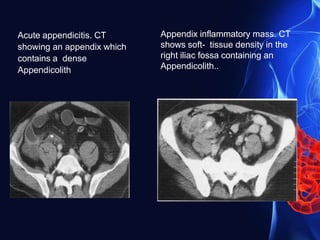

Acute appendicitis. CT

showing an appendix which

contains a dense

Appendicolith

Appendix inflammatory mass. CT

shows soft- tissue density in the

right iliac fossa containing an

Appendicolith..